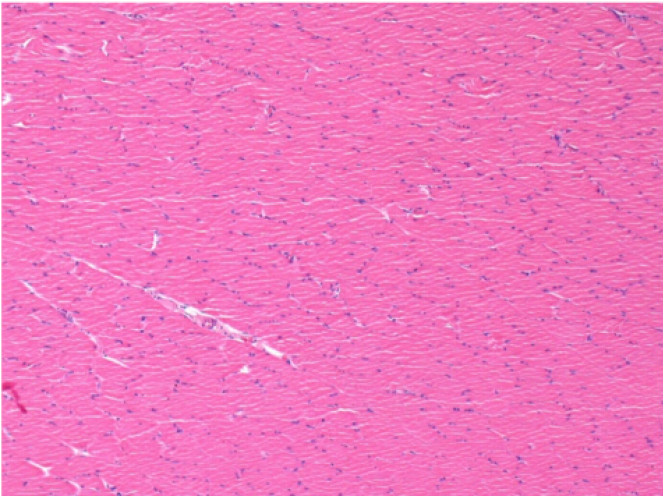

Controllo

Dopo iniezione di NaCl 0.5%

Commento : Niente da dichiarare dopo iniezione di soluzione fisiologica salina.

Sx:Pretibiale-Non trattato

Dx:Pretibiale-Dopo 0.1 ml NaCl 0.9% IM